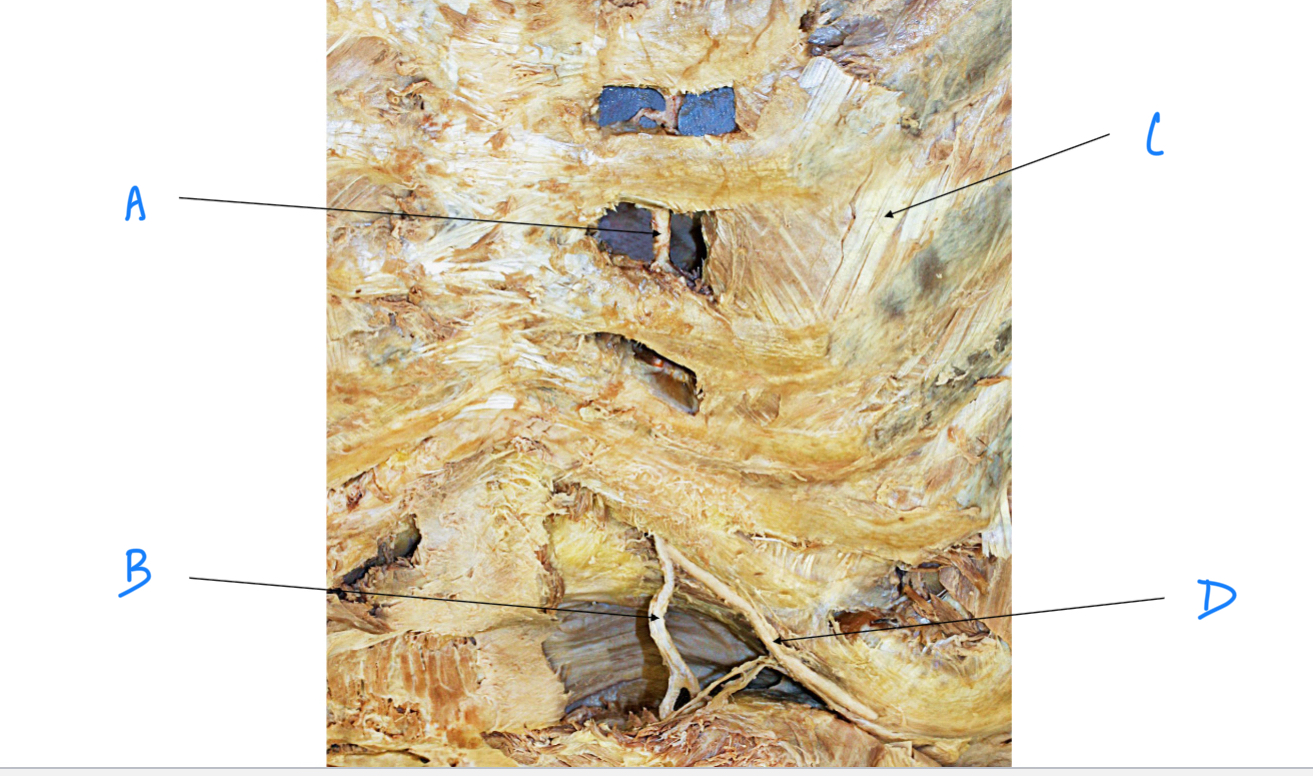

A. Identify structure

Transverse foramen; Vertebral a.

B. Identify structure; What goes through this feature?

Transverse process

C. Identify structure